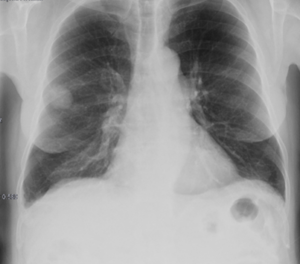

Radiografías de tórax en proyección posteroanterior y en proyección lateral (bipedestación).